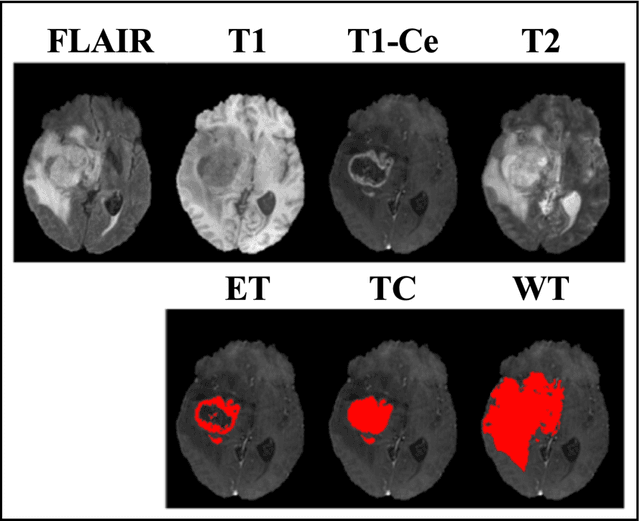

Abstract:We developed a deep ensemble learning model with a radiomics spatial encoding execution for improved glioma segmentation accuracy using multi-parametric MRI (mp-MRI). This model was developed using 369 glioma patients with a 4-modality mp-MRI protocol: T1, contrast-enhanced T1 (T1-Ce), T2, and FLAIR. In each modality volume, a 3D sliding kernel was implemented across the brain to capture image heterogeneity: fifty-six radiomic features were extracted within the kernel, resulting in a 4th order tensor. Each radiomic feature can then be encoded as a 3D image volume, namely a radiomic feature map (RFM). PCA was employed for data dimension reduction and the first 4 PCs were selected. Four deep neural networks as sub-models following the U-Net architecture were trained for the segmenting of a region-of-interest (ROI): each sub-model utilizes the mp-MRI and 1 of the 4 PCs as a 5-channel input for a 2D execution. The 4 softmax probability results given by the U-net ensemble were superimposed and binarized by Otsu method as the segmentation result. Three ensemble models were trained to segment enhancing tumor (ET), tumor core (TC), and whole tumor (WT). The adopted radiomics spatial encoding execution enriches the image heterogeneity information that leads to the successful demonstration of the proposed deep ensemble model, which offers a new tool for mp-MRI based medical image segmentation.

Abstract:Purpose: To develop a U-Net segmentation uncertainty quantification method based on spherical image projection of multi-parametric MRI (MP-MRI) in glioma segmentation. Methods: The projection of planar MRI onto a spherical surface retains global anatomical information. By incorporating such image transformation in our proposed spherical projection-based U-Net (SPU-Net) segmentation model design, multiple segmentation predictions can be obtained for a single MRI. The final segmentation is the average of all predictions, and the variation can be shown as an uncertainty map. An uncertainty score was introduced to compare the uncertainty measurements' performance. The SPU-Net model was implemented on 369 glioma patients with MP-MRI scans. Three SPU-Nets were trained to segment enhancing tumor (ET), tumor core (TC), and whole tumor (WT), respectively. The SPU-Net was compared with (1) classic U-Net with test-time augmentation (TTA) and (2) linear scaling-based U-Net (LSU-Net) in both segmentation accuracy (Dice coefficient) and uncertainty (uncertainty map and uncertainty score). Results: The SPU-Net achieved low uncertainty for correct segmentation predictions (e.g., tumor interior or healthy tissue interior) and high uncertainty for incorrect results (e.g., tumor boundaries). This model could allow the identification of missed tumor targets or segmentation errors in U-Net. The SPU-Net achieved the highest uncertainty scores for 3 targets (ET/TC/WT): 0.826/0.848/0.936, compared to 0.784/0.643/0.872 for the U-Net with TTA and 0.743/0.702/0.876 for the LSU-Net. The SPU-Net also achieved statistically significantly higher Dice coefficients. Conclusion: The SPU-Net offers a powerful tool to quantify glioma segmentation uncertainty while improving segmentation accuracy. The proposed method can be generalized to other medical image-related deep-learning applications for uncertainty evaluation.

Abstract:Purpose: To develop a neural ordinary differential equation (ODE) model for visualizing deep neural network (DNN) behavior during multi-parametric MRI (mp-MRI) based glioma segmentation as a method to enhance deep learning explainability. Methods: By hypothesizing that deep feature extraction can be modeled as a spatiotemporally continuous process, we designed a novel deep learning model, neural ODE, in which deep feature extraction was governed by an ODE without explicit expression. The dynamics of 1) MR images after interactions with DNN and 2) segmentation formation can be visualized after solving ODE. An accumulative contribution curve (ACC) was designed to quantitatively evaluate the utilization of each MRI by DNN towards the final segmentation results. The proposed neural ODE model was demonstrated using 369 glioma patients with a 4-modality mp-MRI protocol: T1, contrast-enhanced T1 (T1-Ce), T2, and FLAIR. Three neural ODE models were trained to segment enhancing tumor (ET), tumor core (TC), and whole tumor (WT). The key MR modalities with significant utilization by DNN were identified based on ACC analysis. Segmentation results by DNN using only the key MR modalities were compared to the ones using all 4 MR modalities. Results: All neural ODE models successfully illustrated image dynamics as expected. ACC analysis identified T1-Ce as the only key modality in ET and TC segmentations, while both FLAIR and T2 were key modalities in WT segmentation. Compared to the U-Net results using all 4 MR modalities, Dice coefficient of ET (0.784->0.775), TC (0.760->0.758), and WT (0.841->0.837) using the key modalities only had minimal differences without significance. Conclusion: The neural ODE model offers a new tool for optimizing the deep learning model inputs with enhanced explainability. The presented methodology can be generalized to other medical image-related deep learning applications.